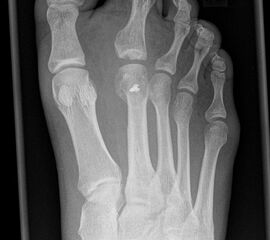

Besondere Bemerkungen zum Beispielbild:

• Schwere Hallux valgus Deformität.

• Die Sesambeine sind luxiert, ebenso das Großzehengrundgelenk. Luxation des Metatarsophalangealgelenks II.

• Degenerative Veränderungen der tarsometatarsalen (TMT) Gelenkreihe, betont TMT II und III.

Zur Vollansicht und zum Lesen der Bildbeschreibung bitte die Bilder anklicken.